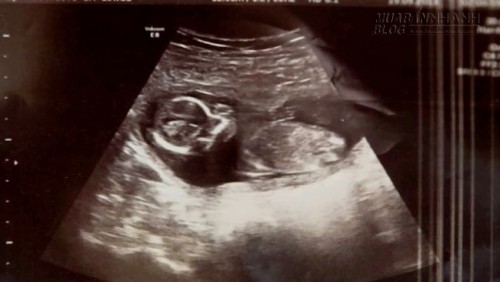

Các bác sĩ tại bệnh viện Rotunda, Dublin đã kiểm tra Michelle một lần cuối trước khi nạo vét, và phát hiện nhịp tim đập ngay trong tử cung của bà mẹ – Michelle vẫn đang mang thai!… “Không thể tin được, chúng ta có nhịp tim đập“, vị bác sĩ trẻ bối rối giải thích với một đồng nghiệp già hơn vừa được gọi tới. Hạnh phúc lại mỉm cười với Michelle một lần nữa.

Hóa ra, bà mẹ Michelle đã mang thai song sinh, và cô mới chỉ mất có một đứa trẻ. Đứa trẻ còn lại đã bị che

khuất bởi máu và dịch do vụ sảy thai, khiến cho các bác sĩ không thể xác định được em trong quá trình siêu âm. Tuy nhiên, làm sao mà thai nhi lại có thể sống sót sau những liều thuốc phá thai và lượng rượu lớn mà Michelle uống vì quá đau khổ? Điều đó ngay đến các chuyên gia y học cũng không thể nào giải thích nổi.